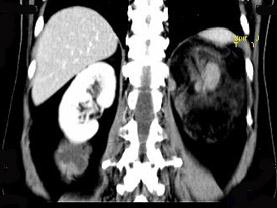

问题 女,64岁,左侧腰部胀痛,行CT扫描,下列说法正确的是 ( )

选项 A、考虑为左侧肾上腺来源的髓样脂肪瘤 B、考虑为腹膜后来源的脂肪肉瘤 C、该病灶密度不均匀,其内可见脂肪密度影,且呈不均匀强化 D、考虑为左肾来源的血管平滑肌脂肪瘤 E、左肾区可见一巨大的占位性病灶,境界较清楚,胰腺尾部受压向前推移

答案 CDE